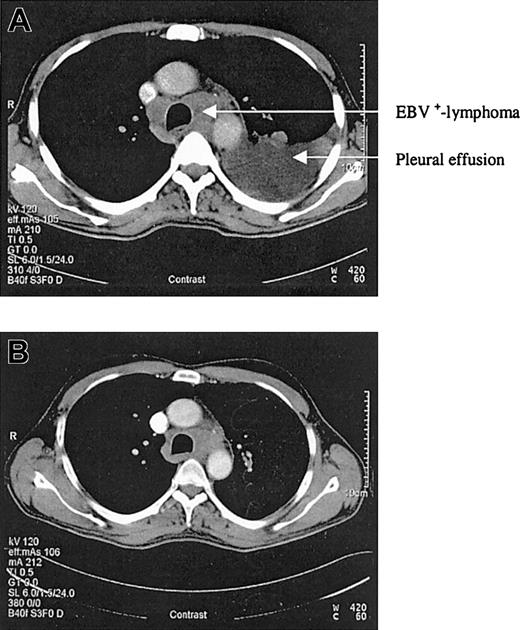

We report a case of acute EBV-associated B-cell diffuse large-cell lymphoma developing shortly after successful treatment of relapsed hairy cell leukemia. In 1998, a 46-year-old patient presented with splenomegaly, leukocytopenia, and thrombocytopenia. The peripheral blood smear demonstrated atypically appearing lymphocytes, resembling hairy cells. The bone marrow biopsy confirmed the diagnosis of hairy cell leukemia by May-Grunwald-Giemsa (MGG) staining, alkaline phosphatase antialkaline phosphatase (APAAP), and immunophenotyping with 85% cells positive for CD103. The patient was treated with continuous intravenous infusions of cladribine (3 mg/m2) for 7 days. His blood counts nearly normalized over the next months, and follow-up bone marrow biopsies confirmed a complete remission. However, in December 2002 a progressive leukocytopenia was detected and in January 2003 a relapse of the hairy cell leukemia was diagnosed by bone marrow biopsy with a 39% infiltration of the bone marrow. Cladribine was initiated again as salvage therapy for 7 consecutive days (3 mg/m2). At 3 weeks after completing the chemotherapy cycle, the patient developed fever, dyspnea, and cough. A computed tomography (CT) scan of the chest revealed typical aspergillosis infiltrates and pleural effusions. The aspergillus antigen in the serum, however, was always negative. Surprisingly, in several blood cultures and in the pleural effusion, high amounts of EBV DNA were detectable by polymerase chain reaction (115 000 genome equivalents/mL in the serum and 950 000 genome equivalents/mL in the pleural effusion). Broad spectrum antibiotics, voriconazole, and cidovir were initiated, leading to clinical improvement and regression of lung infiltrates and pleural effusions. To assess the pneumonia, a control CT scan was performed in April, which revealed regress of infection but also a new mediastinal mass and multiple new cervical lymph nodes (Figure 1A). The biopsy of a cervical lymph node revealed a CD20+ B-cell diffuse large-cell lymphoma that was EBV-associated with expression of latent membrane protein 1 (LMP-1) and EBV nuclear antigen 2 (EBNA-2+) (Figure 2). There was no sign of an infiltration by the hairy cell leukemia in the respective lymph node. At this time the hairy cell leukemia was in complete remission, measured by peripheral blood and bone marrow cytomorphology as well as multiparameter immunophenotyping. In this patient there was no previous history of congenital immunodeficiency. In addition, to exclude an HIV infection an HIV test was performed, which was negative. CD4 counts during this period of time, however, were not measured.As the infection was still not under definitive control and the patient's performance status was reduced, we felt that chemotherapy was not feasible. Therefore, a monotherapy with anti-CD20 monoclonal antibody (rituximab) was initiated at a dose of 375 mg/m2. Currently, the patient is in good general condition and follow-up CT scans revealed a good partial response 3 weeks after 4 applications of rituximab (Figure 1B).

CT scans before and after rituximab application. (A) CT scan of the chest in April 2003. (B) Control CT scan after 4 applications of rituximab showing a good partial response.